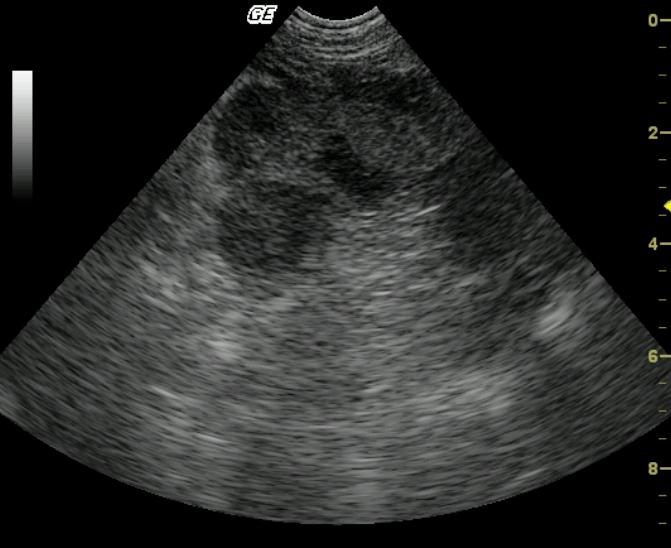

Coarse architecture is noted in both the spleen and liver with irregular capsular contour, echogenic and irregular tissue striations with nodular changes. This universal deviation from parenchymal architecture in both organs suggests a neoplastic process in both liver and spleen. The linear echogenic focus in the near field is a core biopsy needle.

Infiltrative and sclerosing splenic and hepatic pathology, likely neoplastic. Minor potential for aggressive inflammatory disease.

Fibrosarcoma, liver and spleen